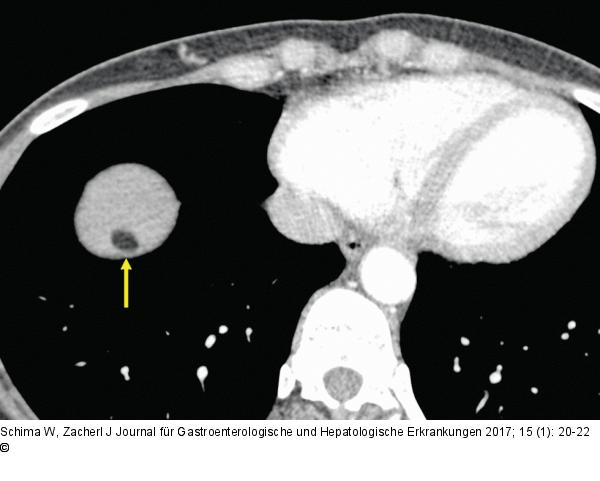

Abbildung 1b: Hypodense Raumforderung Die axiale Kontrastmittel-verstärkte MDCT zeigt eine hypodense Raumforderung in der rechten Leber unmittelbar subdiaphragmal. Die Dichtewerte betragen -84 HU, was typisch ist für Fett (eine flüssigkeitsgefüllte Zyste hätte eine Dichte von ca. 0 HU). |

Die axiale Kontrastmittel-verstärkte MDCT zeigt eine hypodense Raumforderung in der rechten Leber unmittelbar subdiaphragmal. Die Dichtewerte betragen -84 HU, was typisch ist für Fett (eine flüssigkeitsgefüllte Zyste hätte eine Dichte von ca. 0 HU). |